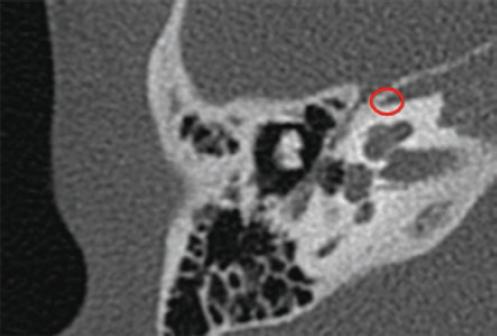

Figura 3 Gusher grave. Oído derecho (corte axial) con la cóclea completamente quística y el vestíbulo muy dilatado (partitura incompleta tipo I).